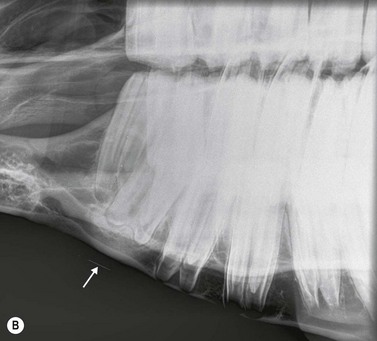

Intra-oral oblique projections (Figs 13.1913.20)

These projections, where a flexible film package or cassette is placed into the oral cavity, represent a modification of the bisecting angle technique used widely in human dental imaging. They have the advantages that there is no superimposition of structures from the contralateral side of the skull, and can also give good detail of the interdental bone and alveolar crest region. However, in the author’s experience, these projections can be difficult to obtain in standing sedated horses, due to difficulties keeping the film in place within the oral cavity.

Fig. 13.20 (A) Intra-oral radiograph of a maxillary cheek teeth row.

image

(B) Intra-oral radiograph taken intra-operatively during a dental extraction procedure. A small bone-opacity fragment can be seen in the rostral aspect of the alveolus (arrow).

The use of human dental film packs4 or of improvised cassettes made of vinyl7 or heavy-duty black polythene1 has been described for intra-oral projections in horses. Pre-packed human dental film is often only large enough to image one or two cheek teeth on each radiograph, and this is a major disadvantage, particularly because the affected tooth is not commonly identified prior to the radiographic examination. Improvised cassettes can be made into a suitable shape for the equine oral cavity (circa 10 × 25 cm) by cutting down film and card-mounted intensifying screen(s) before double wrapping them in closely fitting, light-proof bags e.g., of heavy-duty black polythene, and sealing the edges with light-proof adhesive tape.1 The disadvantages of this system include the time taken to prepare the above materials, poor film/screen contact and the need for wet processing of films.

A self-retaining, full-mouth speculum is used to open the mouth of the heavily sedated or anesthetized horse, and the film is placed in the oral cavity, parallel to the hard palate (Fig. 13.19). If using a small sized film, it must be placed at the level of the tooth of interest. For teeth of mature or older horses, the X-ray beam is directed at an angle of 50°–60° to the horizontal, but to examine the longer reserve crowns of young horses, increased incident angles (70°–80°) are required (Fig. 13.19). The centering point is somewhere between the level of the facial crest and up to 6 cm dorsal to the facial crest, depending on the length of the tooth being radiographed i.e., in younger horses, a more dorsal centering point is required compared to aged horses with short reserve crowns.